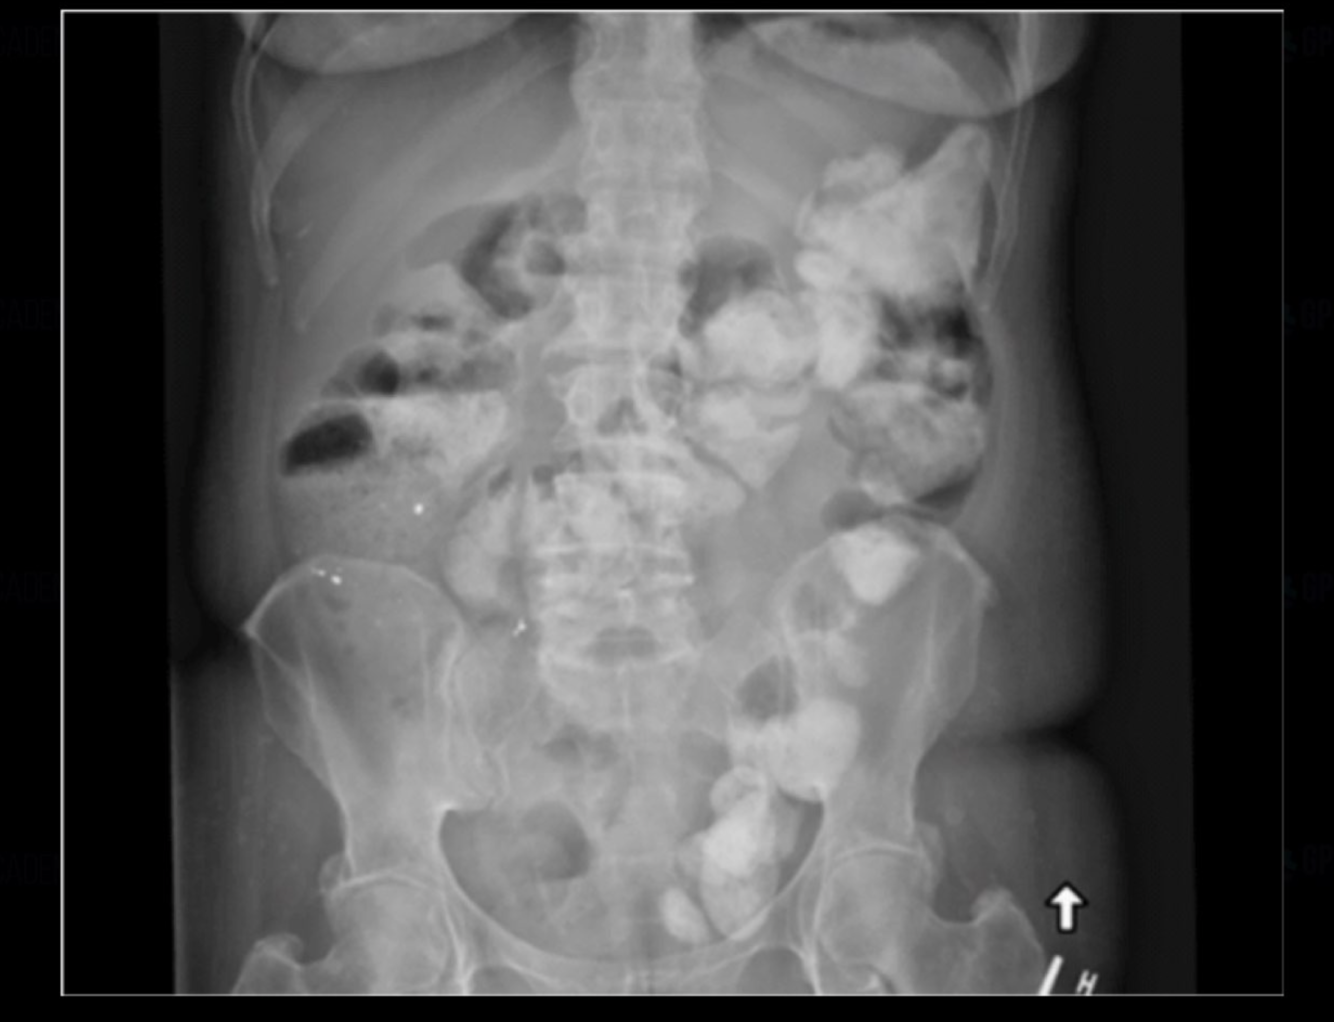

small bowel obstruction

large bowel obstruction

constipation